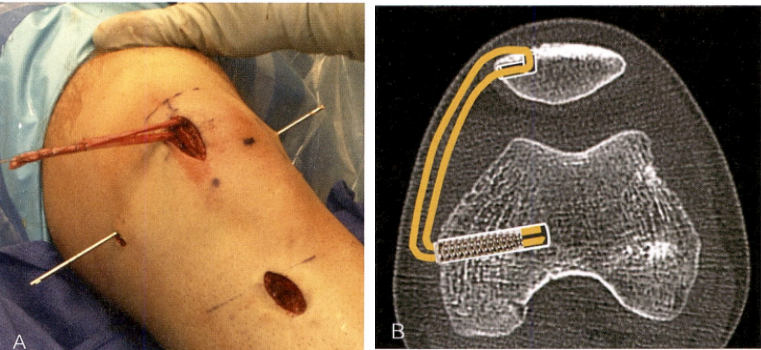

1、内侧髌股韧带(MPFL)重建术:在膝关节0°- 30°屈曲时,MPFL是限制髌骨向外侧移位最主要的韧带,其发生损伤(撕裂、拉伸)时会导致髌骨失去稳定向外侧脱位,因此,髌骨脱位时要行MPFL重建术。

术后 2 ~ 3 周的主要目标是缓解疼痛和肿胀,并建议佩戴膝关节支具提供稳定和运动限制(通常 2 ~ 3 周内膝关节屈曲不超过 90°)。